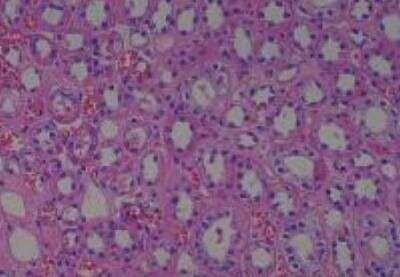

Scientific Data Images for Human Multi Tissue MicroArray (Normal Adjacent)